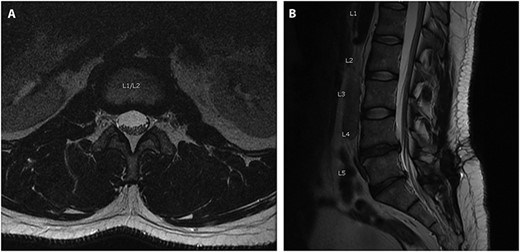

On post-operative day 2, the patient began having urinary retention, bilateral leg pain and numbness in the left L5 distribution. Magnetic resonance imaging (MRI) showed a T12-L2 subdural fluid collection measuring ~8 mm in depth and exerting a mass effect on the distal spinal cord and cauda equina (Fig. 2). The patient was urgently taken back to the operating room for L1-L2 decompressive laminectomy. The thecal sac was under considerable tension and when an incision was made through the dura, the cerebrospinal fluid (CSF) appeared to be under pressure. The epidural space was inspected and no hematoma was noted. A lumbar drain was left in the subdural space. The drain was kept in place for 3 days. The patient progressed well with his strength and sensation, except for some residual numbness in the left toes. The patient was discharged home.

Axial (A) and sagittal (B) T2 MRI scan obtained post-operatively showing a subdural hygroma (arrow), cephalad to the site of fusion, which caused symptoms of cauda equina syndrome.